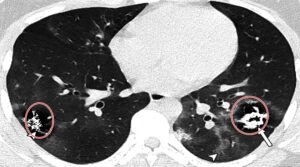

Μια εικόνα-χίλιες λέξεις στην οποία φαίνονται οι βλάβες που έχει προκαλέσει ο κοροναϊός στους πνεύμονες ανήλικων ασθενών οι οποίοι ΔΕΝ είχαν υποκείμενα νοσήματα ανήρτησε στον προσωπικό του λογαριασμό στο Facebook ο επίκουρος καθηγητής στο Τμήμα Υγιεινής και Επιδημιολογίας της Ιατρικής Σχολής του ΕΚΠΑ και μέλος της επιτροπής των εμπειρογνωμόνων, Γκίκας Μαγιορκίνης.

«Μία εικόνα χίλιες λέξεις. Αξονικές τομογραφίες νέων κάτω από 18 έτη με Covid-19 (18 ετών, 15 ετών, 14 ετών και 8 ετών). Κανένας ασθενής δεν είχε υποκείμενα νοσήματα ή ανοσοκαταστολή. Οι ασθενείς δεν χρειάστηκαν συμπληρωματικό οξυγόνο, διασωλήνωση ή ΜΕΘ. Πρόκειται για απλά-κοινά περιστατικά Covid-19. Ωστόσο έχουν πολύ «εντυπωσιακές» βλάβες και είναι άγνωστο τι θα προκαλέσουν αυτές οι βλάβες σε βάθος χρόνου. Για την πλειονότητα του κόσμου το ερώτημα είναι απλό: Θέλουν να υποβάλουν τους πνεύμονές τους σε αυτές τις βλάβες για να δουν αν αντέχουν; Και αν αντέξουν την πρόκληση (όπως προβλέπεται ότι θα αντέξουν οι περισσότεροι νέοι) θέλουν να δουν πόσα χρόνια ή αντοχές έχασαν στην πορεία; Με το εμβόλιο προστατεύουμε τους πνεύμονές μας από βαρύτατη καταπόνηση».